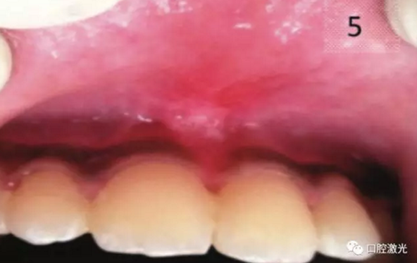

術(shù)后即刻

術(shù)后10日

在激光系帶延長(zhǎng)或整形手術(shù)中,激光其實(shí)不是切割軟組織,而是通過(guò)激光能量氣化軟組織。因此,激光手術(shù)的不適感是相對(duì)較低的。一些嬰兒或兒童在手術(shù)過(guò)程中進(jìn)入睡眠狀態(tài)。并且通過(guò)激光外科手術(shù),能最大程度上減少出血,甚至不出血。由于激光本身有生物刺激的功能,因此整個(gè)愈合的過(guò)程也是十分迅速的。

加快愈合

術(shù)后無(wú)癥狀,不易復(fù)發(fā)